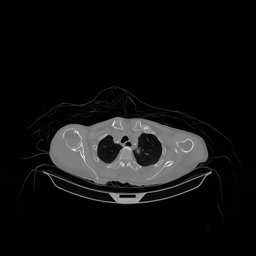

The results for simulated noisy data are shown in Fig. 2. The first and third rows display two representative slices from the test set, and the second and fourth rows present the corresponding error maps. The traditional WCE method suppresses cupping artifacts and recovers some missing anatomical structures but still shows noticeable deviations from the ground truth. Predictions from the four diffusion-based models demonstrate a markedly improved ability to restore anatomical structures. Among them, cDDPM fails to fully reconstruct the patient bed and retains residual noise in its outputs. This noise is attributable to an incomplete reverse denoising process rather than residual Poisson noise, as evidenced in our noise-free experiments (Fig. 5 in the Appendix). PatchDiffusion, diffusionGAN, and I2SB achieve similar visual quality, with I2SB producing the cleanest and most consistent reconstructions.

Quantitative results in Tab. V further confirm I2SB’s superiority over conventional deep learning methods such as FBPConvNet and Pix2pixGAN across RMSE, PSNR, and SSIM. Compared to other diffusion models—including cDDPM, PatchDiffusion, and cLDM—I2SB delivers higher image quality, while diffusionGAN achieves comparable quantitative performance. However, I2SB demonstrates a significant advantage in inference efficiency, as summarized in Tab. IV.